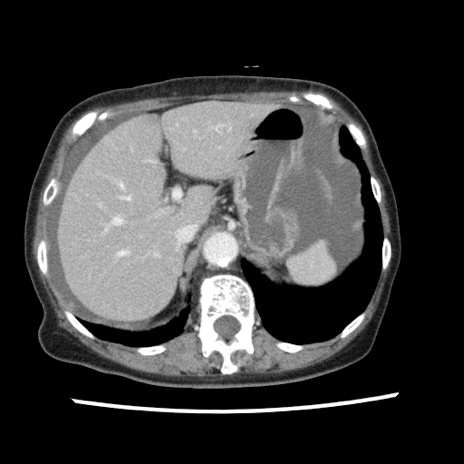

症例1(横断像)

【症例】80歳代女性

【主訴】腹痛

【現病歴】8時間前から腹痛あり来院。

【既往歴】糖尿病、脂質異常症、子宮体癌にて子宮全摘術

【身体所見】意識清明・会話良好だが腹痛で苦悶様、全腹部にわたって反跳痛と圧痛あり

【データ】WBC 13600、CRP 0.14、LDH 224、CK 90